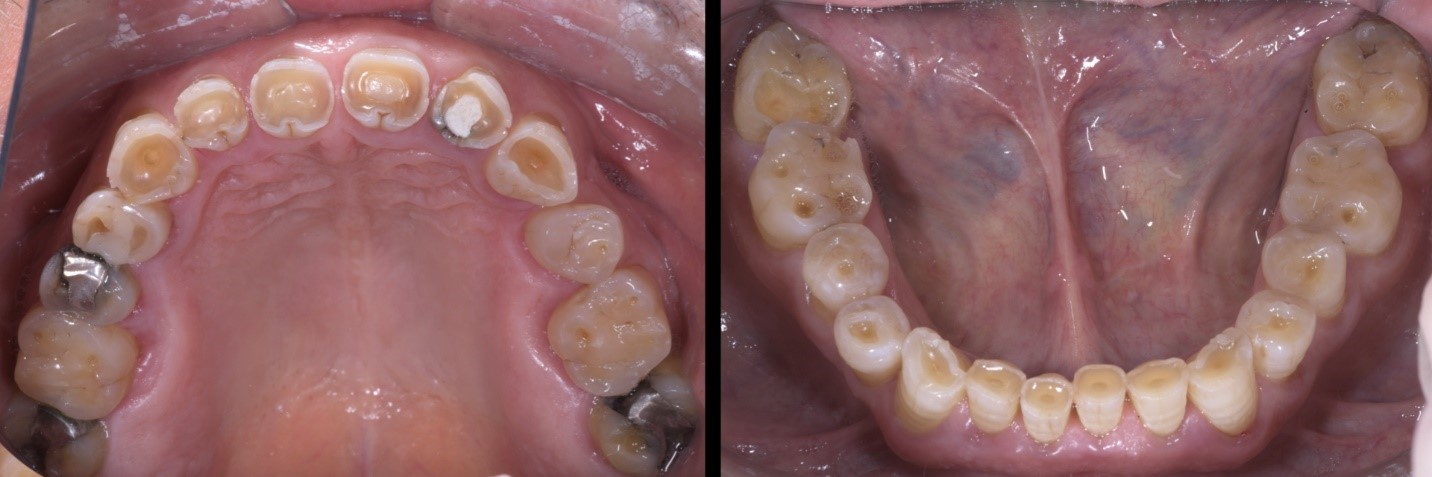

Fig. 1a e 1b

Il Paziente, di anni 69, si presenta alla mia osservazione con forti limiti estetico-funzionali dovuti a dentatura fortemente usurata.